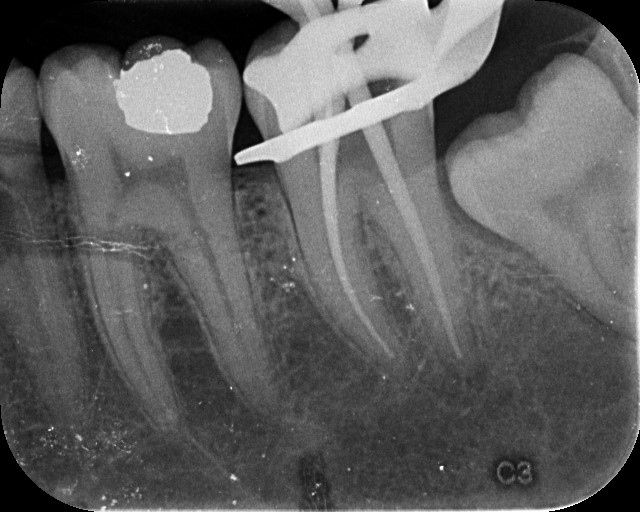

Also known as an apicoectomy, this procedure is performed when infection or inflammation persists at the tip of a tooth’s root, even after root canal treatment. We gently access the root end, remove the infected tissue, and seal the area to prevent future problems-all with the help of magnification and precision tools.

Unlike traditional techniques, our procedure is guided by high-powered dental microscopes, giving our specialists enhanced visibility into the smallest details. This level of precision helps us: